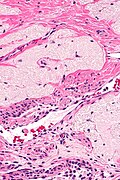

Ablated_endometrium. H&E stain. | |

| LM | endometrium completely or partially replaced by hyaline material and fibrosis |

Microscopic

Features:

- Endometrium completely or partially replaced by:

- Hyaline material, fibrosis.

UTERUS, UTERINE CERVIX, TOTAL HYSTERECTOMY: - SUPERFICIAL FIBROSIS AND HYALINE CHANGE OF THE UTERINE LINING -- COMPATIBLE WITH PRIOR ABLATION. - UTERUS WITH LEIOMYOMAS. - UTERINE CERVIX WITHIN NORMAL LIMITS.